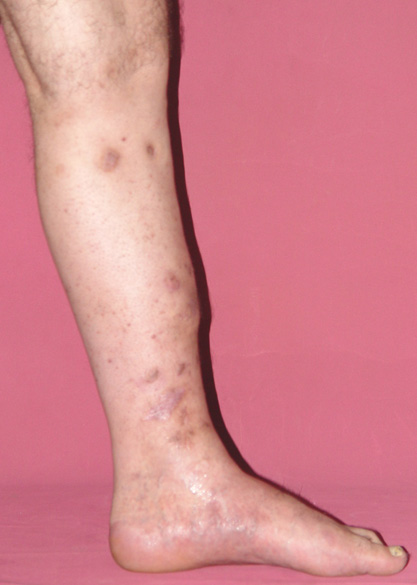

Chronic osteomyelitis leads to necrosis of bone and soft tissues. Dead bone is a nidus which hosts pathogenous microorganisms. Defence mechanisms of the host is usually not in optimum condition to deal with microorganisms. Antibiotics can’t reach the infection site because blood flow is disrupted. For these reasons, dead bone has to be completely removed by radical debridement.

Appropriate radical debridement necessitates excision of all necrotic bone and soft tissues, and frequently causes instability at the involved extremity. The remaining bone and soft tissue defect has to be fixed and reconstructed. The distraction osteogenesis method of Ilizarov is used successfully for achievement of union, correction of the deformity, elimination of limb length inequality and reconstruction of segmental bone defects.